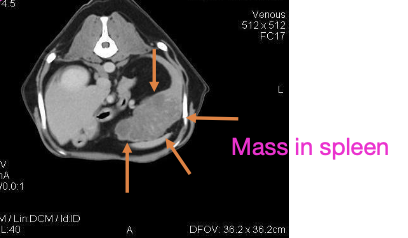

what STS is chemotherapy indicated for?

-grade 3 tumors

-metastatic disease

-intra-abdominal disease

-some subtypes (histiocytic, hemangiosarcoma, rhabdomyosarcoma)